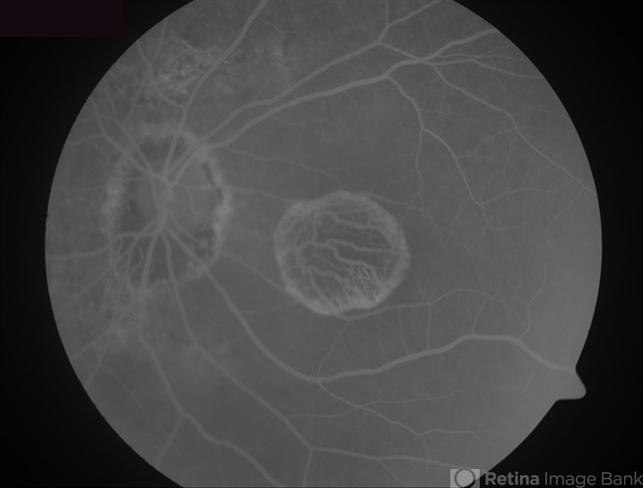

- geographic atrophy, dry age-related macular degeneration (dry AMD)

- Geographic atrophy due to AMD - fluorescein angiogram.